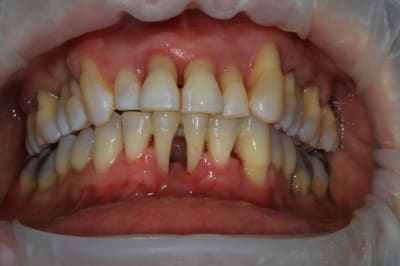

et pour ce cas, pas d'augmentation (à priori) de la Dv, donc diminution, de la hauteur des incisives max. et mand., afin d'essayer de retrouver une ligne de sourire correcte ( qui soit agréable pour la patiente et surtout moins nocive).

petit boulot de ce jour, "coronoplastie de sauvage", afin d'essayer de supprimer les contacts nocifs... ensuite endo 24/25/26.

en occlusion, ça parait moins destructeur, la suite mardi prochain.

surtout dans des cas comme celui là où il y a des mylolyses bilatérales et une double occlusion.

Sur une occlusion qui ést du genre un coup a gauche , un coup a droite, son calage était au départ sur le secteur incisif.

Elle se servait du bloc ant comme un point d appuis pour se faire sa translation postérieure.

Bref on voit mieux sur ces photos que ce sera le haut qu il faudra couronner en fonction du bas qui lui n'est pas dégueulasse .